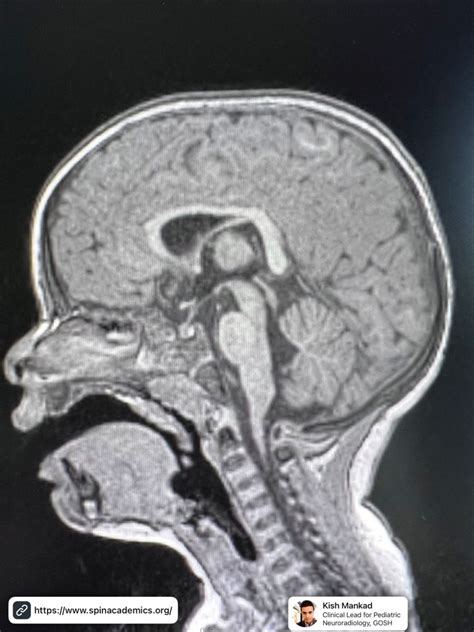

The corpus callosum is divided into four distinct regions, moving from anterior to posterior: the rostrum, the genu, the body (or trunk), and finally, the splenium. As the most posterior and thickest part of the entire structure, the splenium of corpus callosum plays a disproportionately large role in brain function. It acts as a bridge that enables the left and right hemispheres to synchronize their activity, ensuring that the brain operates as a unified whole rather than two separate processing units.

• Proximity: It lies adjacent to the tela choroidea and the pineal gland, placing it in a delicate central position within the cranium.

The efficiency of the splenium of corpus callosum relies heavily on the quality of its white matter. Myelin, the fatty sheath that insulates these nerve fibers, is what gives white matter its characteristic appearance and its high-speed transmission capabilities. In the splenium, the myelination is particularly dense. This is necessary because the visual stimuli processed in the rear of the brain are incredibly complex and demand near-instantaneous synchronization between the left and right sides of the visual field.